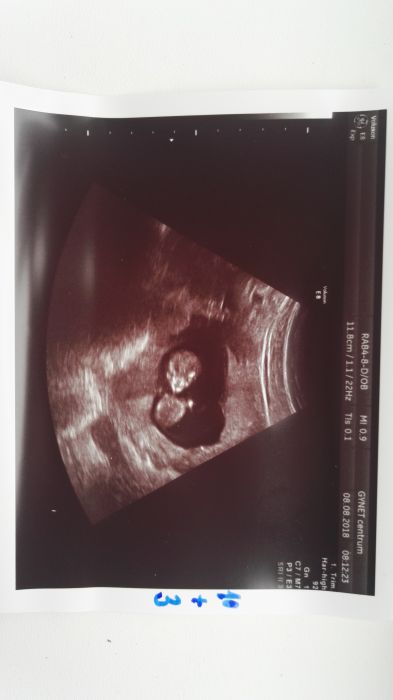

Mam radooost!!! Miminko meri 4 cm az jsem se smala kdyz jsem ho videla na televizi :-D vypada jak mimozemstan hihi ale kraasny

:-D krev jsem ani necitila ze me bere :-) rychlovka a uz mam i tehu prukazku :-) no prikladam utz at se take pobavite :-D

Bobik